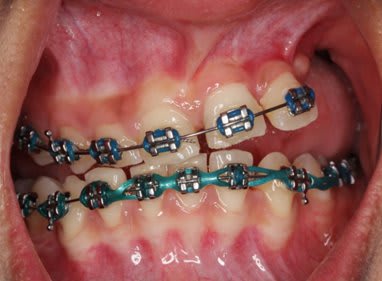

SI joint les photo intra buccal pre traitement et pendant traitement.

Comment expliquer vous le développement ce canting en frontal et de l'open bite en Postérieur ?

Qu'elle est la source du mal ?

Photo 1 on met des brackets et fils un ans plus tard Photo 2

Une seul possibilité a ma connaissance qui explique le canting antérieur et l'open bite postérieur.